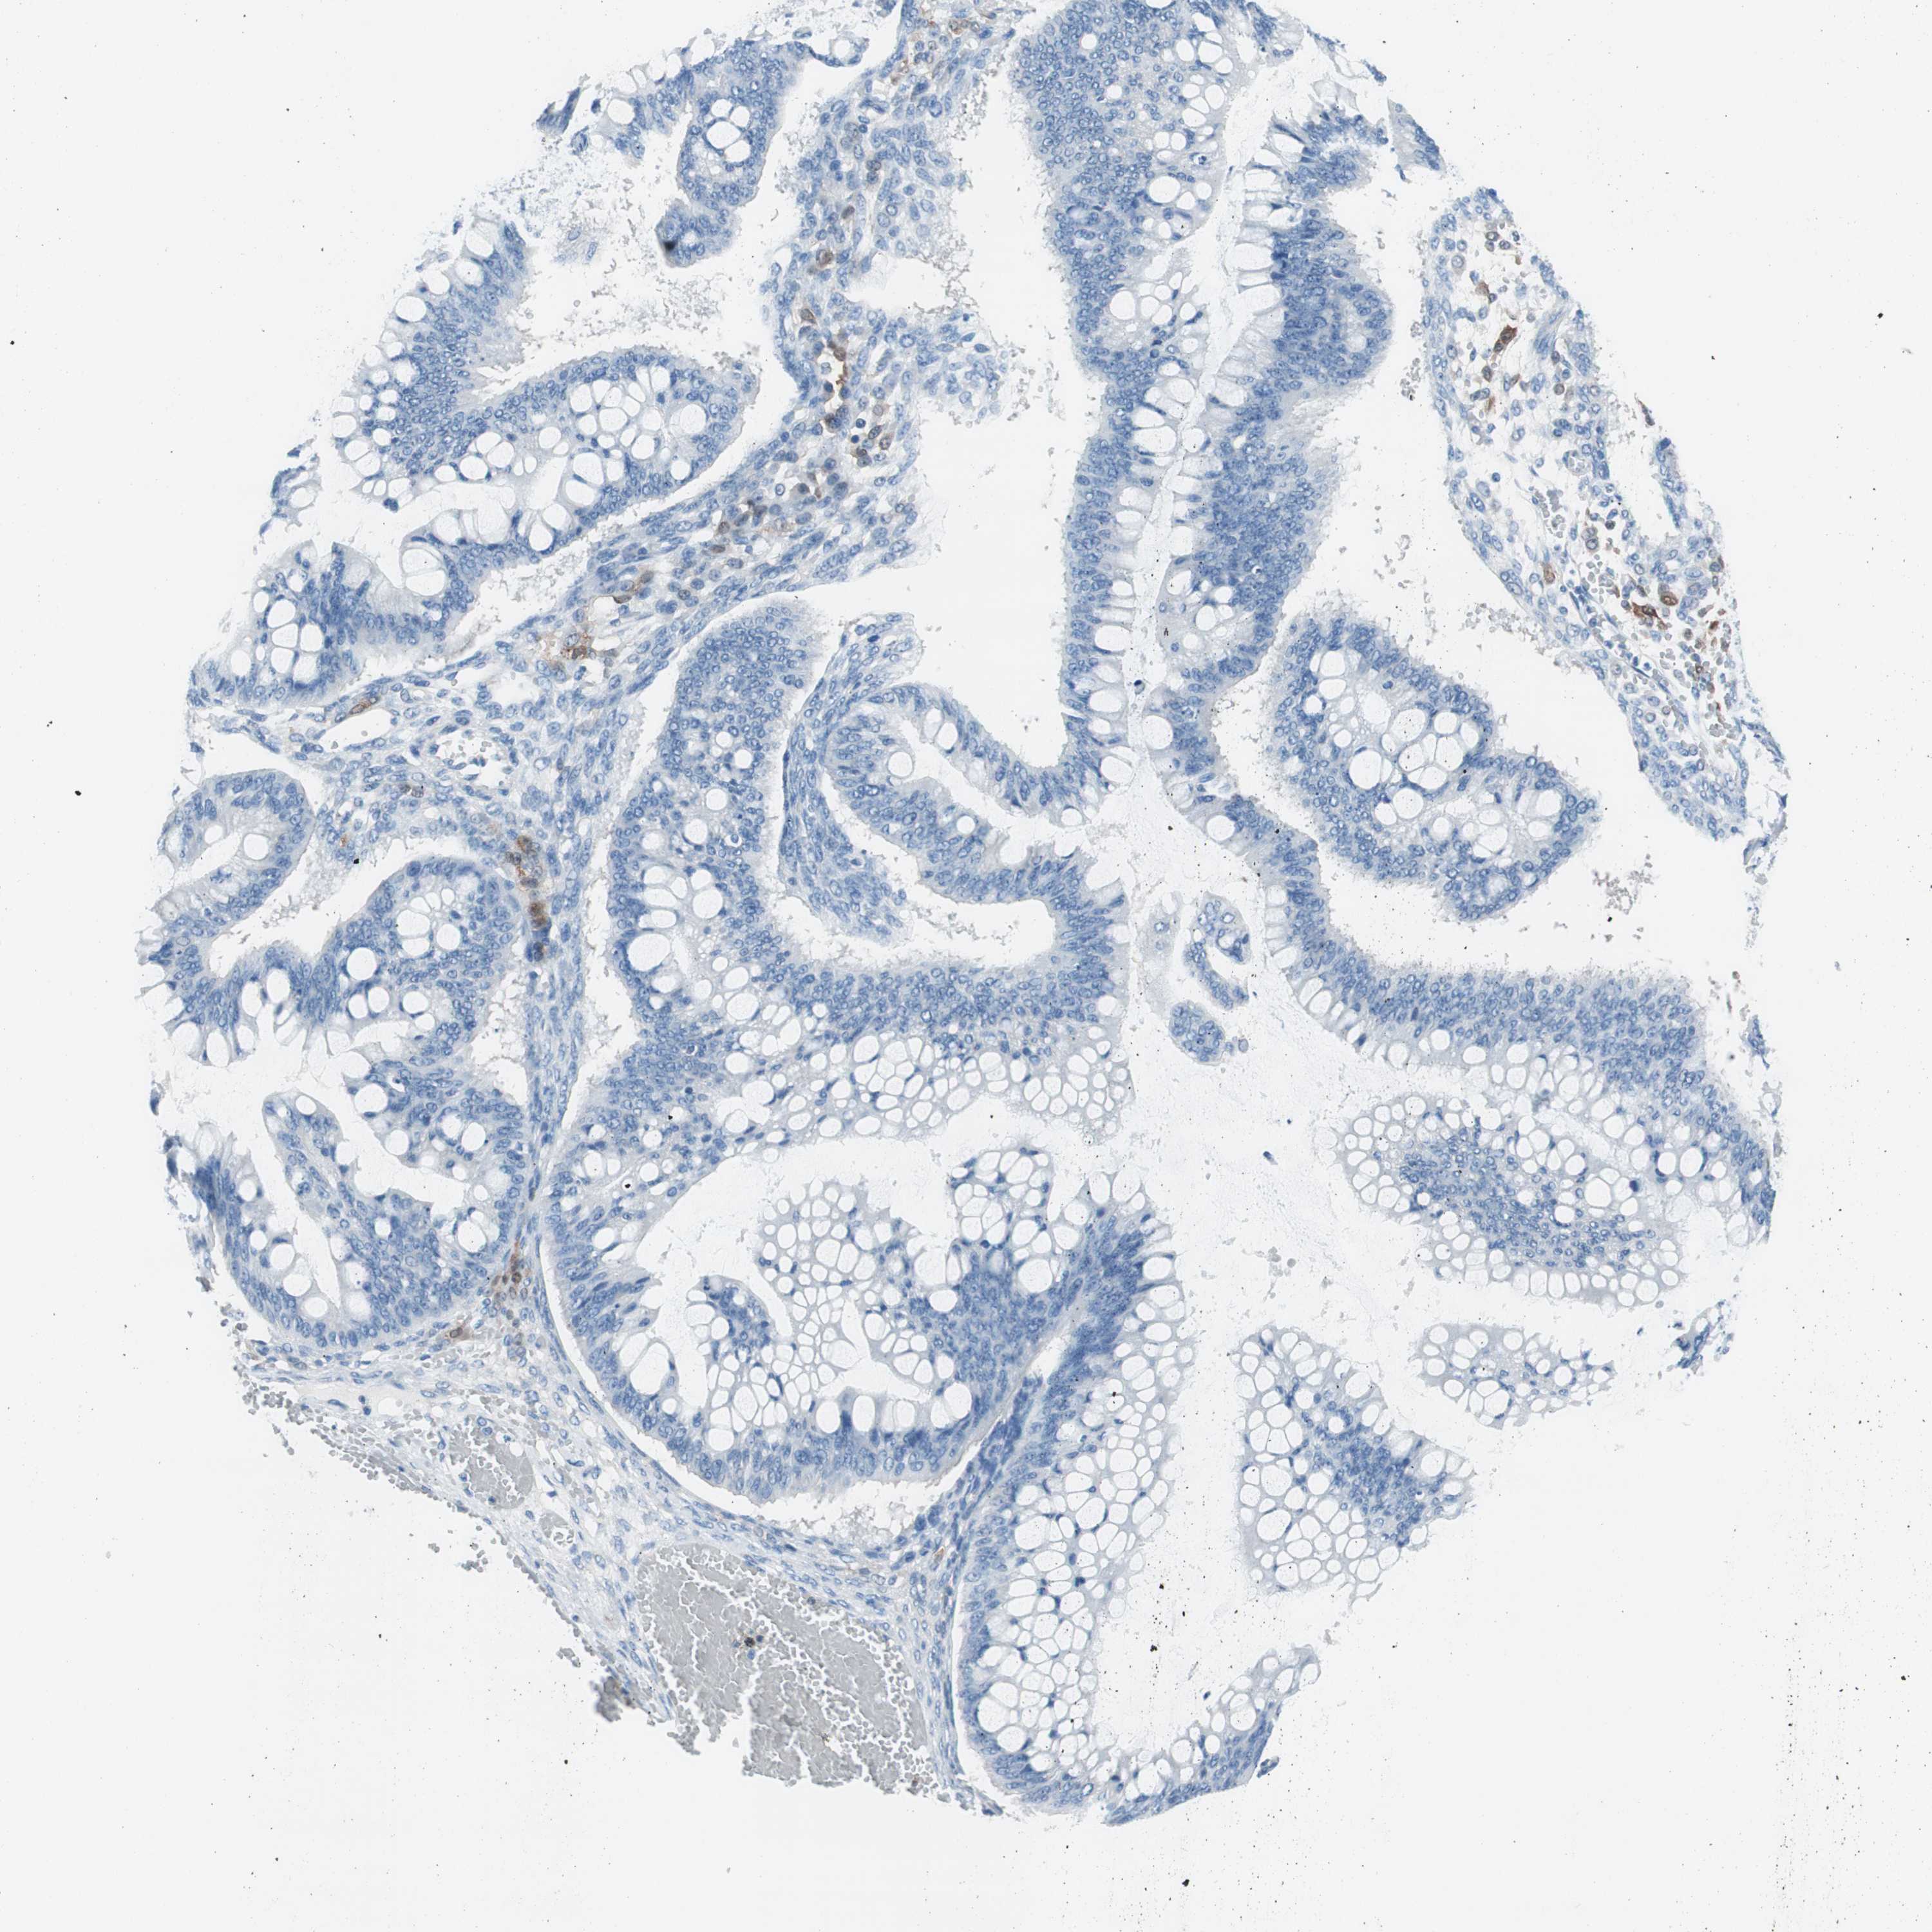

OVARIAN CANCER - Protein expressioni

A mouse-over function shows sample information and annotation data. Click on an image to view it in a full screen mode. Samples can be filtered based on level of antibody staining by selecting one or several of the following categories: high, medium, low and not detected. The assay and annotation is described here.

Note that samples used for immunohistochemistry by the Human Protein Atlas do not correspond to samples in the TCGA dataset.

Antibody stainingi

Antibody staining in the annotated cell types in the current human tissue is reported as not detected, low, medium, or high, based on conventional immunohistochemistry profiling in selected tissues. This score is based on the combination of the staining intensity and fraction of stained cells.

Each image is clickable and will lead to virtual microscopy that enables deeper exploration of all samples and also displays staining intensity scores, fraction scores and subcellular localization as well as patient and tissue information for each sample.

Antibody HPA008055

Staining

High

Medium

Low

Not detected

Intensity

Strong

Moderate

Weak

Negative

Quantity

>75%

75%-25%

<25%

None

Location

Nuclear

Cytoplasmic/membranous

Cytoplasmic/membranous,nuclear

Cystadenocarcinoma, serous, NOS

Carcinoma, endometroid

Carcinoma, NOS

Cystadenocarcinoma, mucinous, NOS